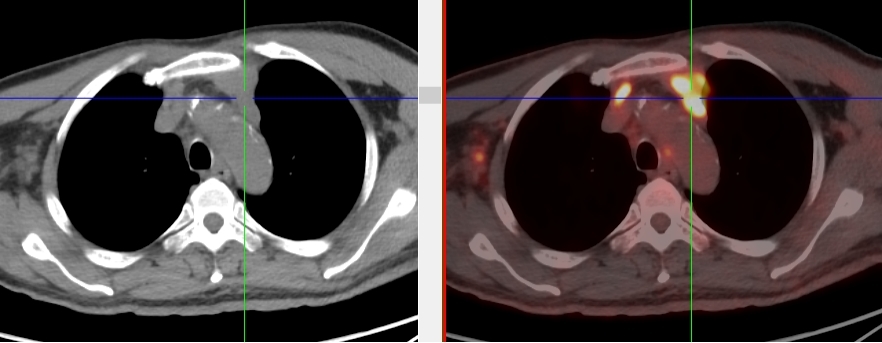

完善胸部強化CT考慮縱隔MT并縱隔、右腋窩及雙肺門多發腫大淋巴結,后行超聲引導下行右腋窩腫物穿刺活檢術,病理首先考慮惡性腫瘤,因穿刺組織局限,腫瘤細胞成分過少,不能明確診斷。

完善PET/CT檢查示:右側腋窩、雙側中下頸部、縱隔、雙側肺門多發MT,建議淋巴結活檢。后患者行右腋窩淋巴結切除活檢術,經北京大學第三醫院病理科會診示:右腋窩淋巴結惡性腫瘤,呈淋巴竇內生長模式,瘤細胞呈上皮樣,異型性明顯,伴中性粒細胞浸潤。結合病史及免疫組化,考慮為SMARCA4(BRG1)缺失的胸部腫瘤,伴神經內分泌標記表達。

本例為罕見病理類型的腫瘤,影像學表現無明顯特異性,診斷困難。強化CT和穿刺病理已基本明確為惡性腫瘤,行PET/CT檢查一是為了全身檢查,完善分期,二是根據PET代謝情況指導進行生物靶區活檢,進一步明確病理診斷。最終,PET/CT除縱隔病變外發現更多頸胸部淋巴結代謝異常,綜合考慮后對腋窩淋巴結進行切除活檢,最終得到病理證實。